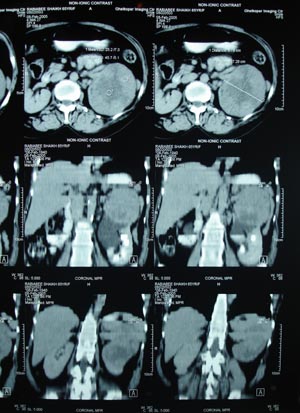

Renal cell carcinoma 2

Left renal cell carcinoma. Solitary mass arising within the renal cell parenchyma, not cystic in nature is most likely to be malignant in nature.In adults mostly it is renal cell carcinoma (In children mostly it is wilms’ tumour)